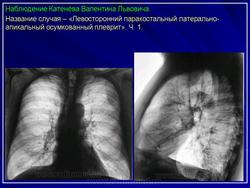

Левосторонний паракостальный осумкованный плеврит.

2. Осумкованный паракостальный плеврит.

Пристеночные (паракостальные) осумкованные плевриты являются результатом неполного рассасывания свободного экссудативного паракостального плеврита или транссудата, свои широким основанием прилежат к поверхности ребер.

В типичных случаях рентгенологическая картина пристеночных осумкований довольно характерна.

Они, скиалогически проявляясь синдромом «ограниченного затемнения», имеют форму теней, примыкающих широким плоским основанием к реберному краю.